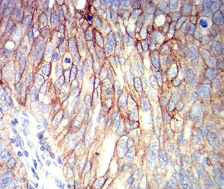

IHC    1/200 - 1/1000